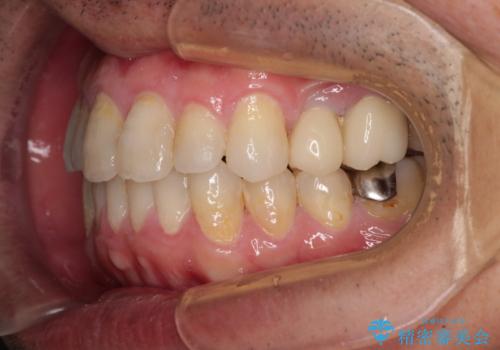

内側に転位した歯とボロボロのむし歯 インビザラインによる矯正治療とむし歯治療

- ボロボロのむし歯とデコボコの歯列を気にして来院された患者様です。

ボロボロとなっていた歯は抜歯が必要な状態でしたが、舌側転位している歯を移動させることで抜歯スペースを埋めることができるため、矯正治療により歯列を整えることとしました。

舌側転位の改善にインビザラインを用いるのはやや難易度が高くなりますが、前歯部のデコボコは軽度であったため、インビザラインによる矯正治療を行うこととしました。

矯正治療後には抜歯が必要な歯に隣接してむし歯となっていた歯をオールセラミッククラウンにて補綴治療を行うこととしました。